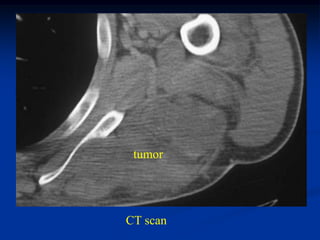

Case #1171

9 year male with desmoid tumor posterior axilla

tumor

CT scan

Axial T-2 MRI